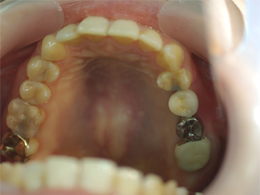

左上の奥歯の骨が少なくてそのままではインプラントを入れられなかったため、オペと同時にサイナスリフトをしました。

今ではしっかり噛めています。骨が極度までない場合でもほとんどがインプラントオペと同時にサイナスリフトが可能です。

奥歯は骨が少なく、骨をつくり、インプラント治療をしました。赤く囲ったところが出来た骨です。